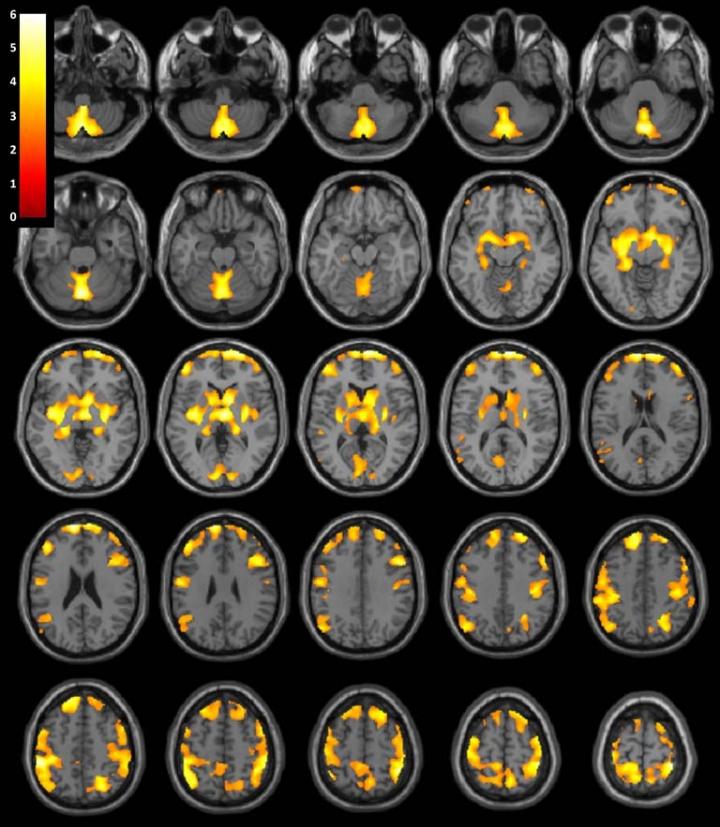

OAK BROOK, Ill. - Stimulant drug abuse has long-term effects on brain volume in women, according to a new study published online in the journal Radiology . Brain structures involved in reward, learning and executive control showed vast changes even after a prolonged period of abstinence from drug use.

"We found that after an average of 13.5 months of abstinence, women who were previously dependent on stimulants had significantly less gray matter volume in several brain areas compared to healthy women," said the study's senior author, Jody Tanabe, M.D., professor of radiology, vice chair of Research, and Neuroradiology Section Chief at the University of Colorado Denver School of Medicine. "These brain areas are important for decision making, emotion, reward processing and habit formation."

The researchers analyzed structural brain magnetic resonance imaging (MRI) exams in 127 men and women, including 59 people (28 women and 31 men) who were previously dependent on cocaine, amphetamines, and/or methamphetamine for an average of 15.7 years, and 68 healthy people (28 women and 40 men) who were similar in age and gender. The MRI results showed that after an average of 13.5 months of abstinence, women who were previously dependent on stimulants had significantly less gray matter volume in frontal, limbic and temporal regions of the brain.

"While the women previously dependent on stimulants demonstrated widespread brain differences when compared to their healthy control counterparts, the men demonstrated no significant brain differences," Dr. Tanabe said.

The researchers also looked at how these brain volume differences were related to behaviors. They found that lower regional gray matter volumes correlated with behavioral tendencies to seek reward and novelty.

"Lower gray matter volumes in women who had been stimulant dependent were associated with more impulsivity, greater behavioral approach to reward, and also more severe drug use," Dr. Tanabe said. "In contrast, all men and healthy women did not show such correlations."